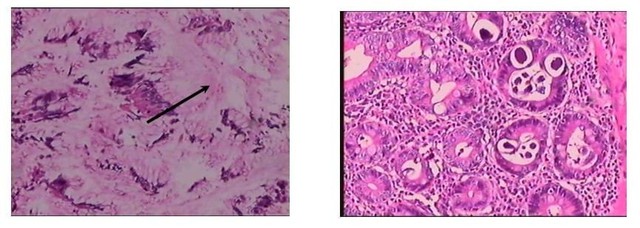

Tuy nhiên, kết quả bất ngờ nằm ở mẫu mô sau khi phẫu thuật. Khi soi dưới kính hiển vi, các bác sĩ Giải phẫu bệnh đã phát hiện ra "thủ phạm" thực sự: Giun lươn đang ký sinh trong niêm mạc ruột non, hoàn toàn không có tế bào ung thư như nghi ngờ ban đầu.

A: Hình ảnh viêm loét dạ dày – B: Hình ảnh giun lươn (Mũi tên) trong ruột non